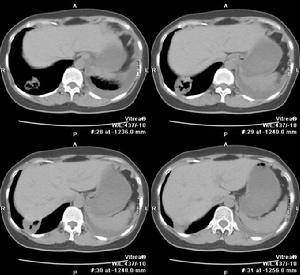

2.CT檢查斷層(包括CT)可更好了解病變範圍、部位、空腔情況。少數膿腫內膿液未排出,表現為圓形塊影,但在可見內有小空洞,真正呈實塊的不多,易誤為腫瘤。纖維化明顯的肺體積縮小,支氣管完全閉塞可有肺不張。可

見葉間胸膜增厚。膿腫破向胸腔形成膿胸或膿氣胸,片上有相應改變。